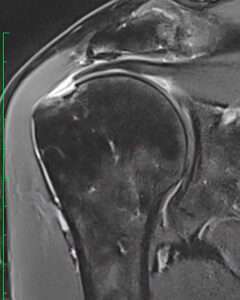

Shoulder: right

Patient: 66 y/o male, right-handed

Progressive pain since 2020

spontaneous progressive pain since 2019 shoulder pain, infiltration with pain improvement.

Symptoms:

pain and weakness

Phys Exam:

ELEV 170°, ABD 80°, ER 30°, IR T10°

Jobe 10+4, ERR 10+3, BPT 15+5, BHT 10+4, Palmup 10+4

ARES +, Yocum +

Score:

VAS 7/10, SSV 51%, ARES 45, CS 50